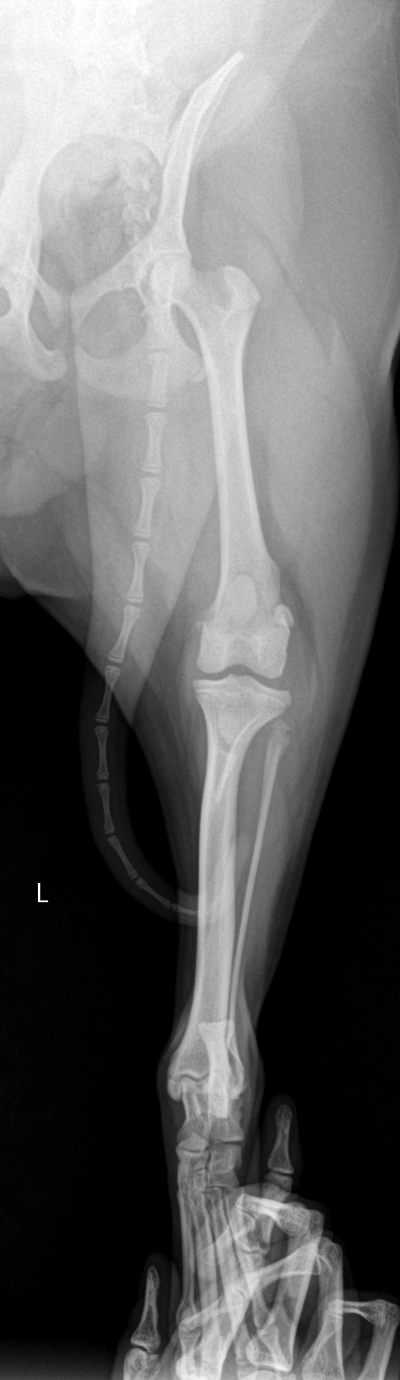

새벽 산책은 남편이 시켰다. 5시 30분에 일어나서 30분간 시키고, 나는 회사 갈 준비를 했다. 퇴근 후 밤에는 내가 산책을 시키곤 했는데, 억지로 외근을 만들어 집에 일찍 들어가려고 노력했다. 그렇게 우린 아침저녁으로 산책만 시키면 되는 줄 알았다. 푸디가 뒷다리를 잘 못쓴다는 사실을 알면서도 병원에 데려가기가 무서웠다. 수술하라고 할까 봐. 중성화 때도 얼마나 마음이 아팠는데, 또 몸에 칼을 대게 하긴 싫었다. 그래서 그냥 모른 척하고 있었는지도 모른다. 그러던 어느 날, 푸디가 정말 뒷다리를 절뚝거리며 걸었다. 가끔 낑낑대기도 하면서, 안 되겠다 싶어서 바로 병원에 갔는데, 수의사는 대퇴골두(엉덩이뼈) 쪽에 이상이 생겼다고 했다. 수술이 불가피하다고 빠른 시일 안에 수술을 하는 것이 좋겠다고 말했다. 혹시나 하는 마음으로 다른 병원에도 가봤지만, 똑같은 말만 반복했다. 하늘이 무너지는 것 같았다. 대퇴골두와 뒷다리 뼈가 연결이 자연스럽게 이어져야 하는데 푸디는 어떤 이유 때문인지 튀어나와 있었다.

엑스레이상에서도 오른쪽과 왼쪽 뒷다리에는 확연한 차이가 있었다. 엉덩이와 뒷다리 뼈가 이어지는 부분에 이미 뼈가 끊어져 알 수 없는 구조물이 붙은 게 보였다. 수술방법은 뼈를 절단하는 것이었다. 사람의 경우는 뼈 대신에 인공 구조물을 넣지만, 강아지는 그냥 절단한 채로도 괜찮단다. 대신 수술 후 케어가 필수적이라고 했다. 뒷다리 한쪽을 쓰지 않으려고 하면 퇴화될 수 있어서 무조건 운동을 시켜야 한다는 것이다. 이것저것 생각할 것도 없었다. 2022년 1월 27일, 푸디 수술 이후 난 직장을 나가지 않고 강아지 돌보는데 전념했다.